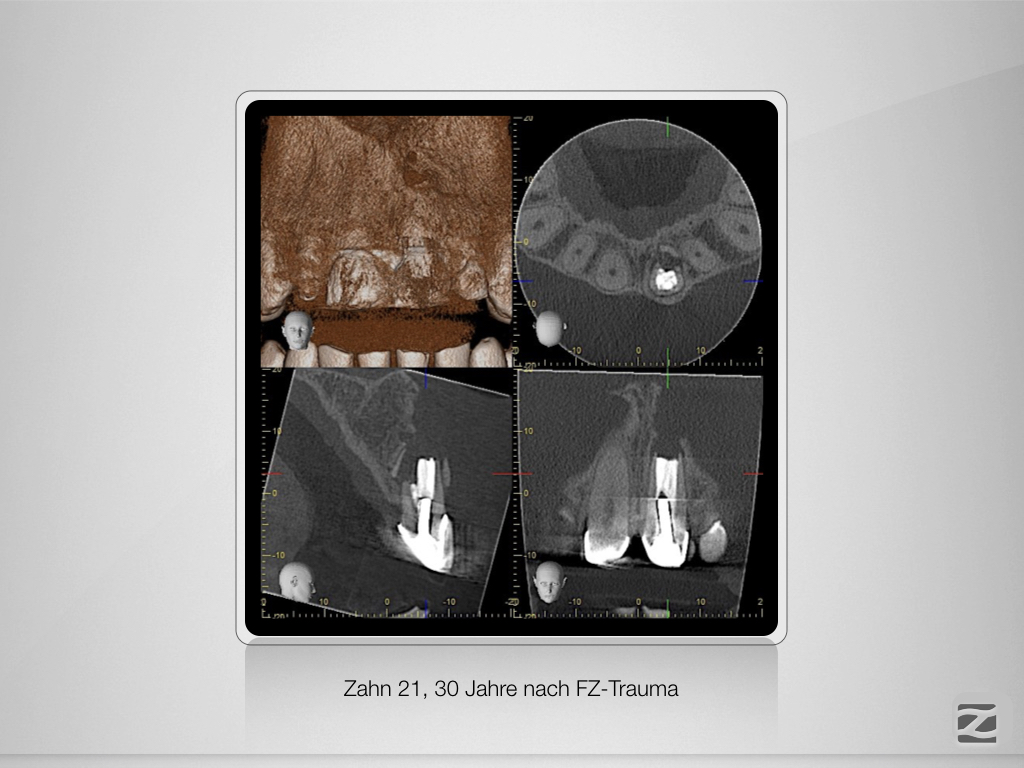

DVT & Ex.002

Entscheidungshilfe